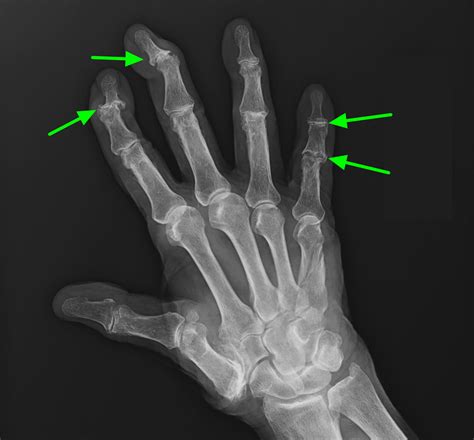

• Arthritis: Osteoarthritis and rheumatoid arthritis can cause inflammation and damage to the shoulder joint, leading to bone spur formation.

• Imaging Tests: Diagnostic imaging tests, such as X-rays, CT scans, or MRI scans, can help visualize the bone spur and assess the extent of the damage. These tests provide detailed images of the shoulder joint and surrounding tissues.

X-ray Uses radiation to produce images of the bones. Identify bone spurs and assess bone structure.

CT Scan Uses X-rays and computer technology to create detailed images of the bones and soft tissues. Provide a more detailed view of the bone spur and surrounding tissues.

MRI Scan Uses magnetic fields and radio waves to produce images of the bones and soft tissues. Assess the condition of the tendons, ligaments, and other soft tissues around the shoulder.